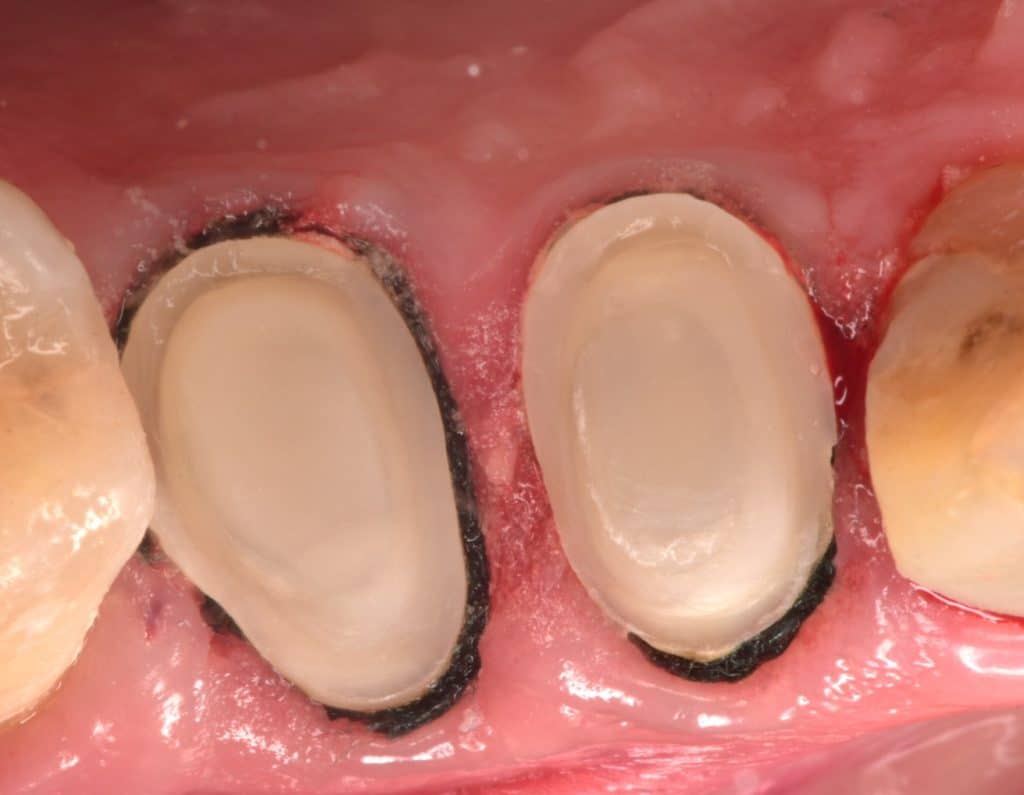

Clearfil SE bond, wetted Ribbond placed inside the cavity surrounded by ever x flow and covered by composite restoration to create the core build up material

Core build up

Preparation done , macro-core buildup for premolars

Cementation day, isolation with rubberdam, biobase air abraded

Buccal view showing the macro-core buildup